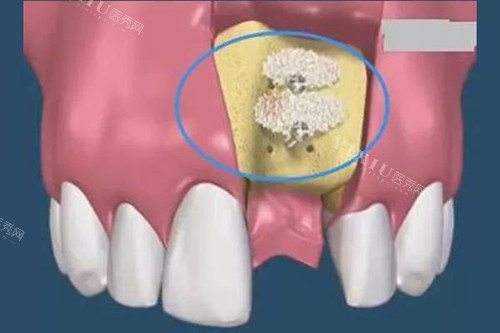

骨增量手术风险高:植骨手术需额外植入人工骨粉,术后感染率增加20%,且需等待6个月骨愈合期;

2. 骨整合效率

SLA表面处理:通过大颗粒喷砂+酸蚀技术,将种植体表面粗糙度提升至Ra2.5μm,骨结合速度较传统种植体提升40%;

平台转移设计:基台直径比种植体小0.5mm,引导骨组织向种植体颈部生长,减少边缘骨吸收。